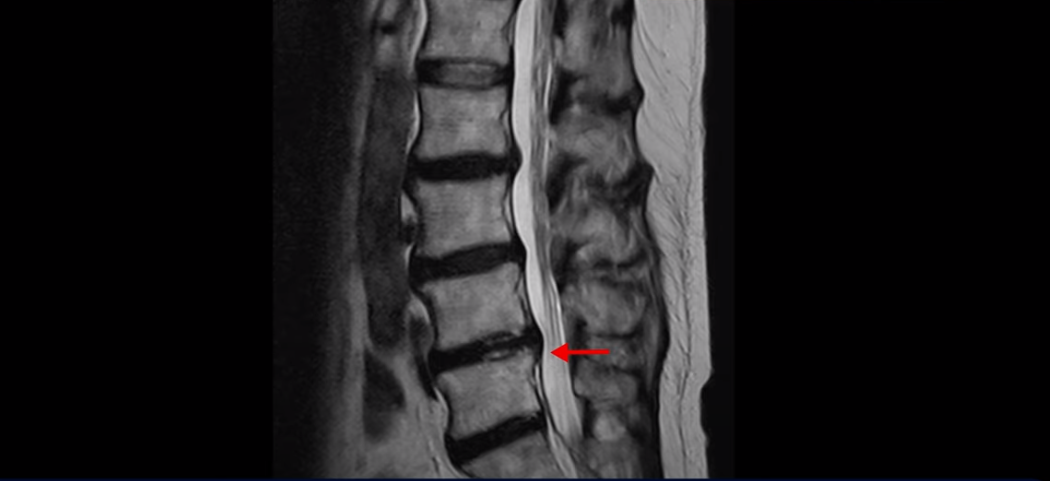

또 4번 5번 마디에 오른쪽으로 찢어져서 밀려나온 디스크 탈출이 보입니다.

밀려나온 수핵이 조금 흘러내려 있습니다.